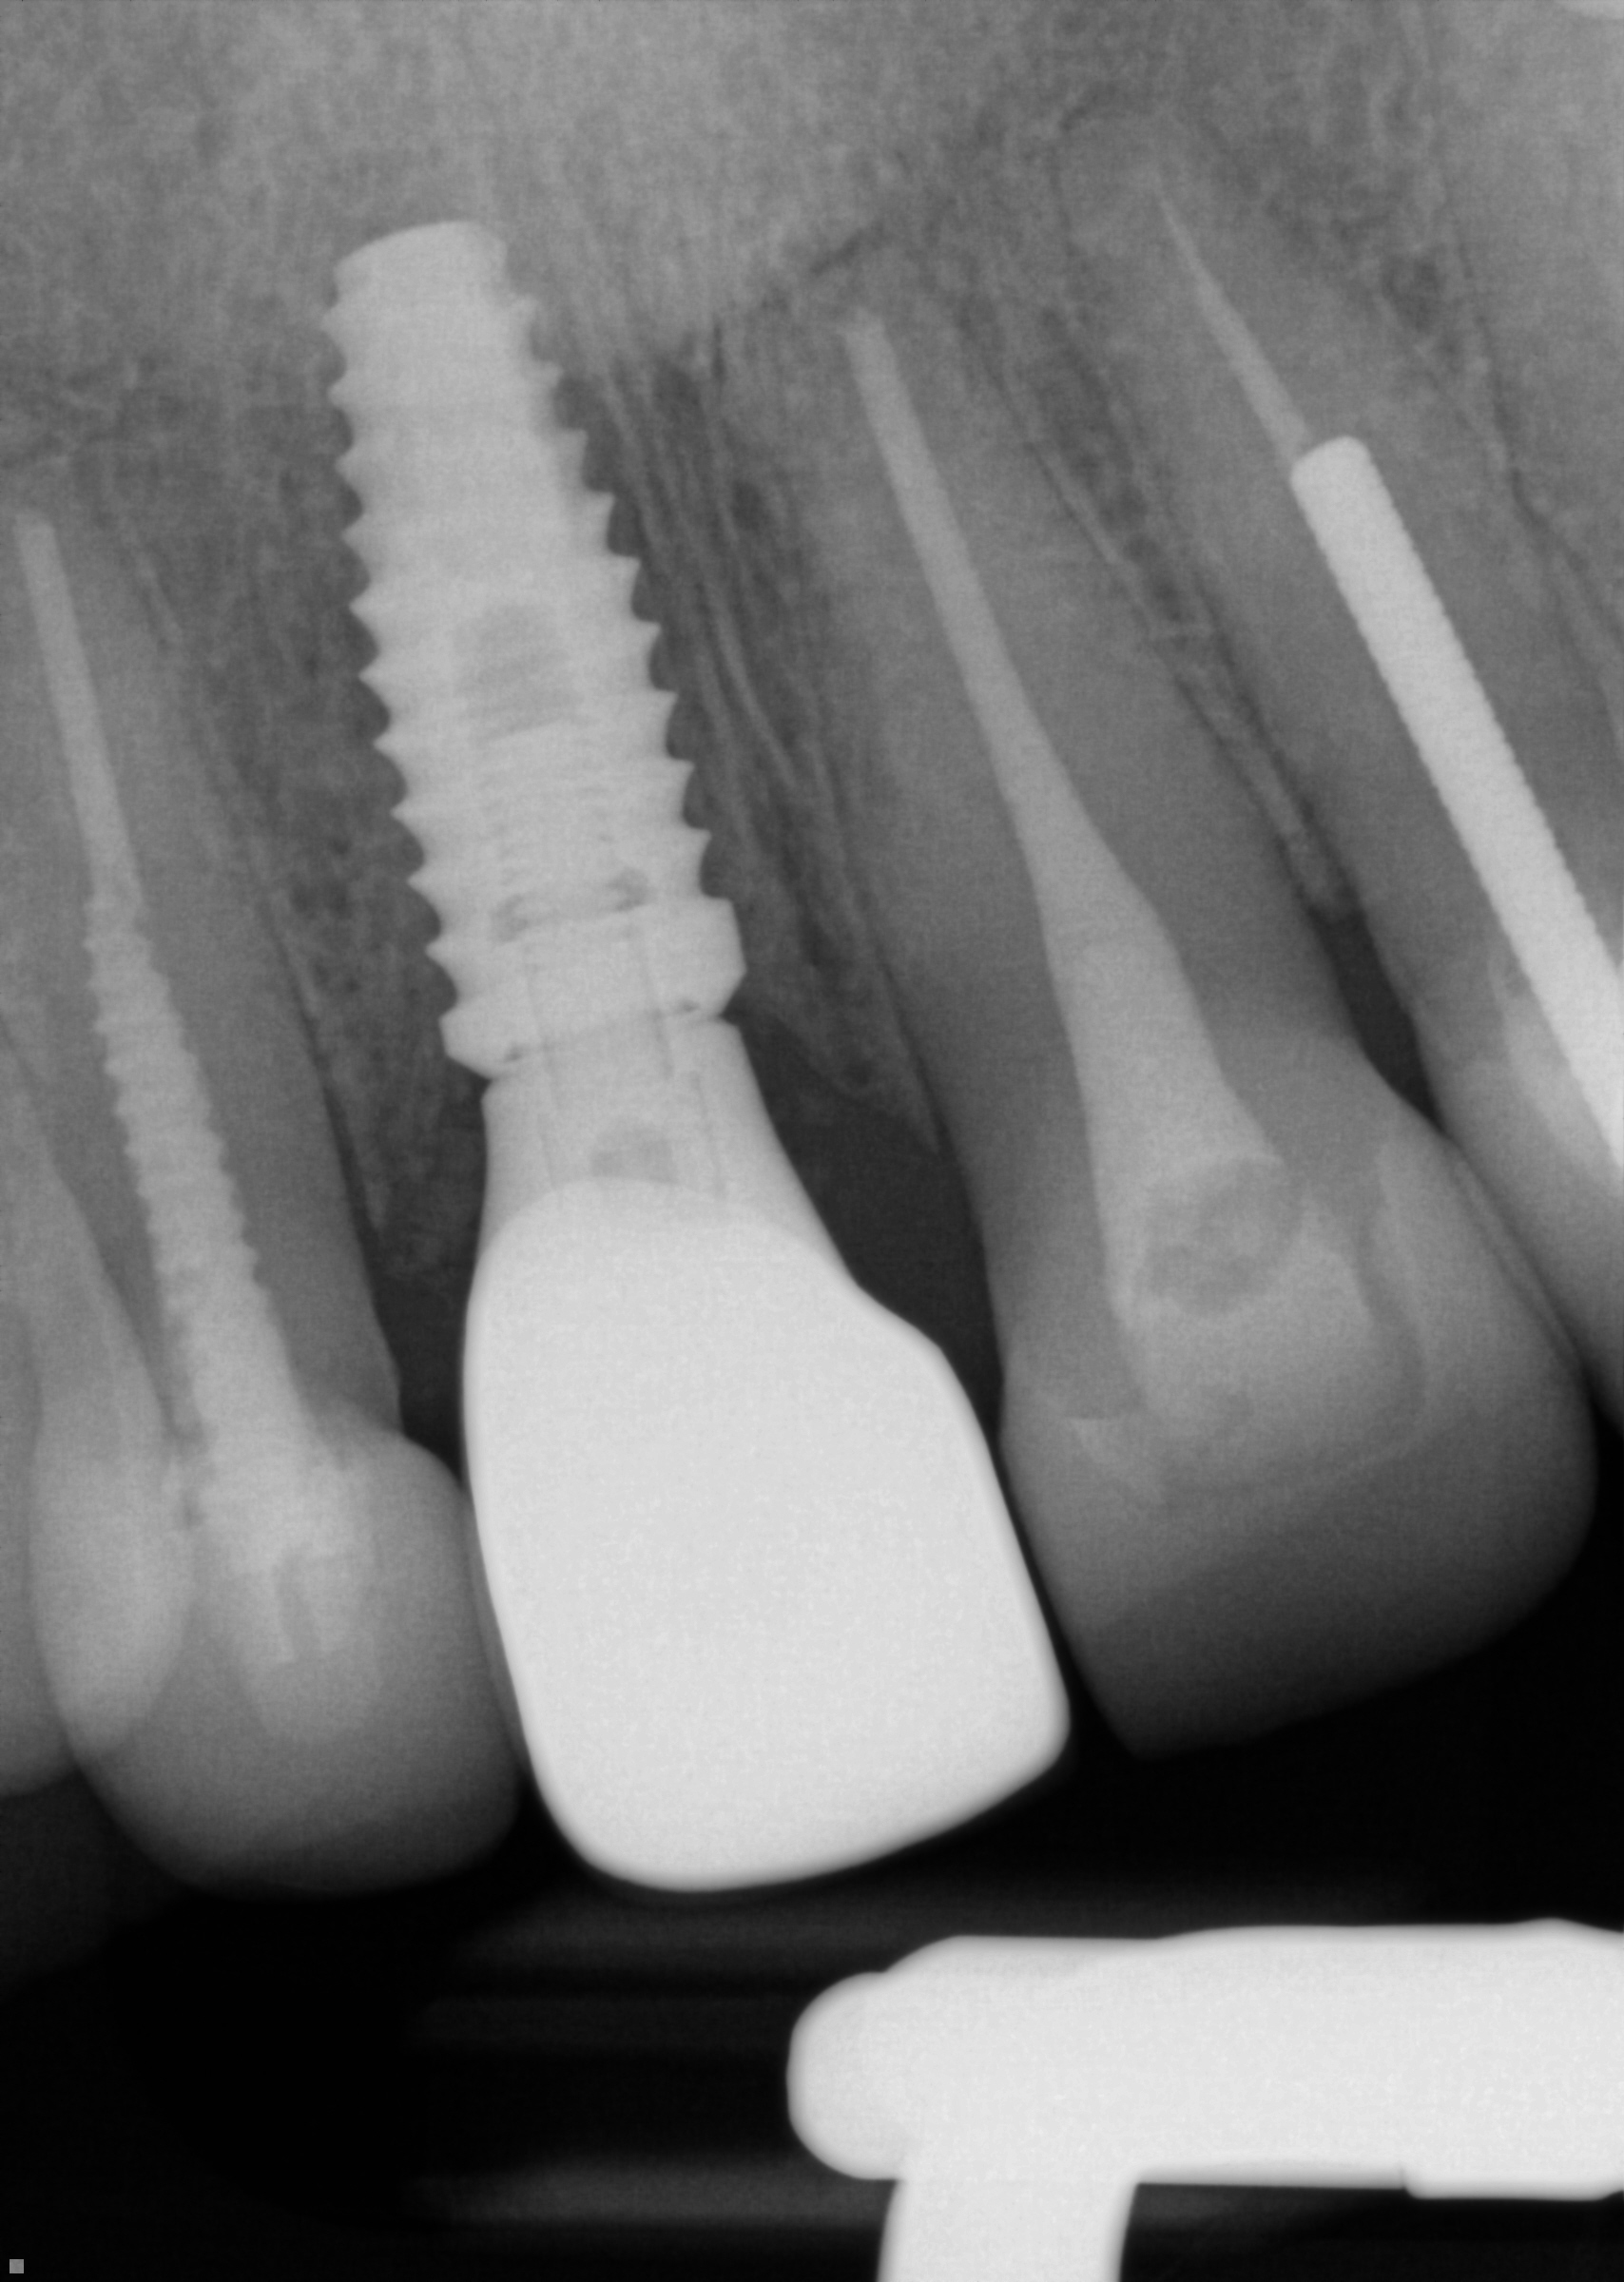

X-rays, or dental radiographs, can help detect and diagnose dental issues early. Two types of x-rays might be recommended during your routine exam. The panorex or full face x-ray is generally recommended every five years. A panorex allows your dentist to visualize the jaw bones, sinuses, roots of the teeth and other head and neck anatomy. Your dentist is trained to detect abnormalities and will let you know if he sees something that requires attention. Bitewing x-rays are generally recommended every 1-2 years. Bitewings can help detect cavities, especially when they are small and in between teeth. Finding cavities when they are small can prevent the need for more expensive dental treatments such as crowns or root canals. Bitewing x-rays also help your dentist visualize the supporting bone around your teeth. Detecting the loss of bone around teeth early is important to maintaining healthy gums.